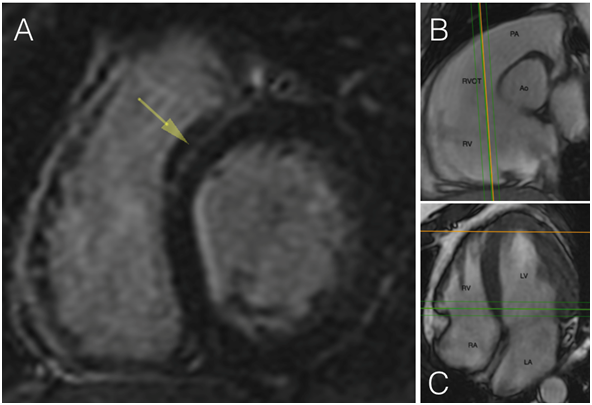

A 21 year-old man was evaluated by a cardiologist in an emergency unit with a three hours history of palpitations, lightheadedness and diaphoresis. Physical examination was unremarkable except for a heart rate of 150 bpm. No laboratory abnormalities were observed.  Electrocardiogram (ECG) showed a wide QRS complex tachyarrhythmia (Figure 1) with monomorphic ventricular tachycardia (VT) criteria. After amiodarona administration, a second ECG showed sinusal rhythm and monomorphic ventricular trigeminism (LBBB pattern with inferior axis) (Figure 2). Transthoracic echocardiogram was unremarkable. In follow-up, ECG and 24 hours ambulatory Holter showed the same of monomorphic ventricular extrasystoles in 30% of the beats. In this context, the diagnosis of idiopathic ventricular tachycardia was suspected. Three weeks later, cardiac magnetic resonance was requested and  basal interventricular septum myocarditis scar between both outflow tract, and systolic dysfunction (LVEF=48%)  was reported (Figure 3). In that context, what is the next step?

Figure 3: CMR. In A we observe a lineal intramyocardial LGE in the bsal portion of interventricular septum, in correlation to the right ventricule outflow tract (B, C). This finding support the posible origen of the extrasystole and VT in relation to the scar.